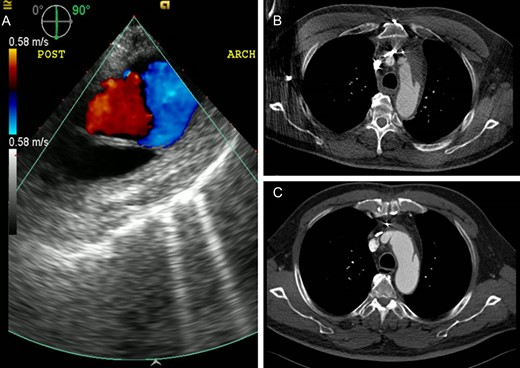

A 79-year-old man with multiple comorbidities presented with acute chest pain, and a computed tomography angiogram (CTA) showed ATAAD extending from the sinotubular junction to the proximal descending thoracic aorta with an intimal tear identified in the ascending but not distal aorta (Fig. 1). The aortic arch was not aneurysmal.

Preoperative computed tomography angiography shows the type A aortic dissection with intimal flap extending from the sinotubular junction to the proximal descending thoracic aorta (A, arrowhead). The primary entry tear is located in the ascending aorta (B, arrow). The re-entry intimal tear is not identified (C).